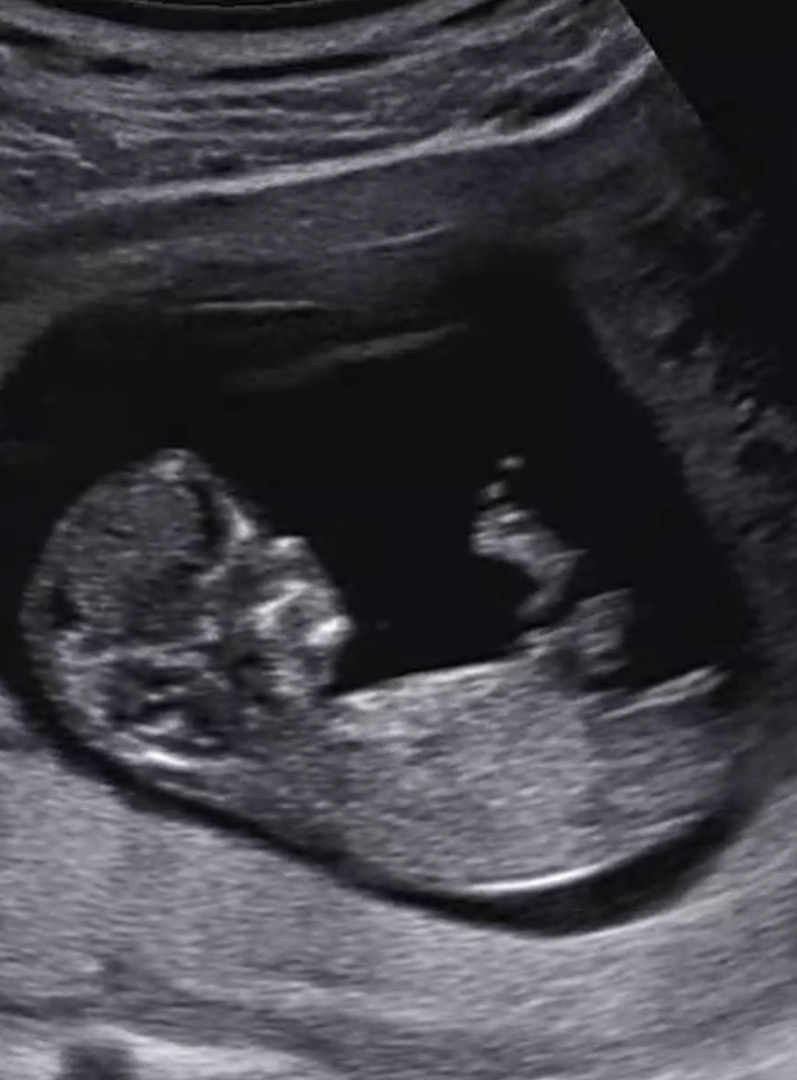

각도법 부탁드려요..🤍

둘째여서 너무 궁금하네요 ㅎㅋㅎㅋ

이 사진은 아들 같아요